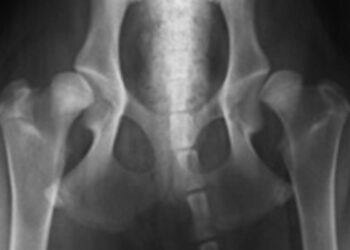

Le mot « dysplasie » signifie « anomalie du développement ». La dysplasie de la hanche est une déformation de l'articulation de la hanche (articulation coxofémorale) qui se produit pendant le développement, c'est à dire pendant la période de croissance de l'animal. Ensuite, Comment soigner la dysplasie chez le chien ...